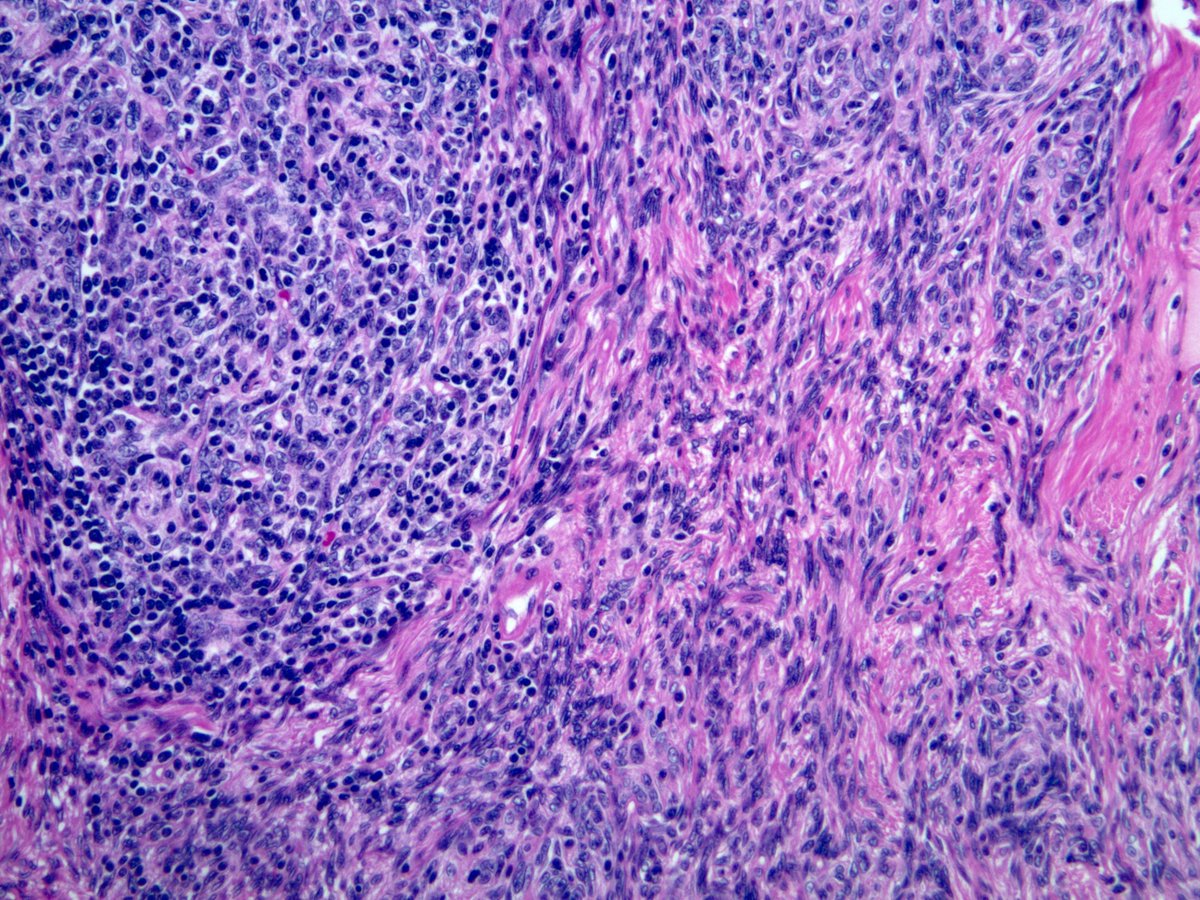

Histological view showing spindle cell proliferation arranged in a Solitary Spindle Cell Xanthogranuloma It occurs mainly in adults. Solitary spindle cell xanthogranuloma occurs with decreasing frequency on the head, neck, upper trunk, or occasionally the extremities of young. Spindle cell xanthogranuloma is a rare variant form of juvenile xanthogranuloma. It presents with a well demarcated nodule composed. Solitary Spindle Cell Xanthogranuloma.

Figure 1 from A Vascularappearing Spindle Cell Xanthogranuloma in a Solitary Spindle Cell Xanthogranuloma Spindle cell xanthogranuloma is a rare variant form of juvenile xanthogranuloma. Solitary spindle cell xanthogranuloma occurs with decreasing frequency on the head, neck, upper trunk, or occasionally the extremities of young. It presents with a well demarcated nodule composed. It occurs mainly in adults. Solitary Spindle Cell Xanthogranuloma.